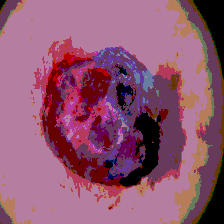

Timely identification and treatment of rapidly progressing skin cancers can significantly contribute to the preservation of patients' health and well-being. Dermoscopy, a dependable and accessible tool, plays a pivotal role in the initial stages of skin cancer detection. Consequently, the effective processing of digital dermoscopy images holds significant importance in elevating the accuracy of skin cancer diagnoses. Multilevel thresholding is a key tool in medical imaging that extracts objects within the image to facilitate its analysis. In this paper, an enhanced version of the Mud Ring Algorithm hybridized with the Whale Optimization Algorithm, named WMRA, is proposed. The proposed approach utilizes bubble-net attack and mud ring strategy to overcome stagnation in local optima and obtain optimal thresholds. The experimental results show that WMRA is powerful against a cluster of recent methods in terms of fitness, Peak Signal to Noise Ratio (PSNR), and Mean Square Error (MSE).